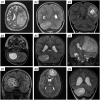

High-grade neuroepithelial tumor with BCOR exon 15 internal tandem duplication (HGNET BCOR ex15 ITD) is a recently proposed tumor entity of the central nervous system (CNS) with a distinct methylation profile and characteristic genetic alteration. The complete spectrum of histologic features, accompanying genetic alterations, clinical outcomes, and optimal treatment for this new tumor entity are largely unknown. Here, we performed a comprehensive assessment of 10 new cases of HGNET BCOR ex15 ITD. The tumors mostly occurred in young children and were located in the cerebral or cerebellar hemispheres. On imaging all tumors were large, well-circumscribed, heterogeneous masses with variable enhancement and reduced diffusion. They were histologically characterized by predominantly solid growth, glioma-like fibrillarity, perivascular pseudorosettes, and palisading necrosis, but absence of microvascular proliferation. They demonstrated sparse to absent GFAP expression, no synaptophysin expression, variable OLIG2 and NeuN positivity, and diffuse strong BCOR nuclear positivity. While BCOR exon 15 internal tandem duplication was the solitary pathogenic alteration identified in six cases, four cases contained additional alterations including CDKN2A/B homozygous deletion, TERT amplification or promoter hotspot mutation, and damaging mutations in TP53, BCORL1, EP300, SMARCA2 and STAG2. While the limited clinical follow-up in prior reports had indicated a uniformly dismal prognosis for this tumor entity, this cohort includes multiple long-term survivors. Our study further supports inclusion of HGNET BCOR ex15 ITD as a distinct CNS tumor entity and expands the known clinicopathologic, radiographic, and genetic features.